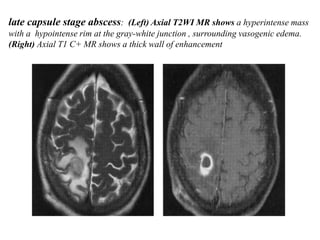

late capsule stage abscess: (Left) Axial T2WI MR shows a hyperintense mass

with a hypointense rim at the gray-white junction , surrounding vasogenic edema.

(Right) Axial T1 C+ MR shows a thick wall of enhancement

late capsule stageabscess: (Left) Axial T2WI MR shows a hyperintense mass with a hypointense rim at the gray-white junction , surrounding vasogenic edema. (Right) Axial T1 C+ MR shows a thick wall of enhancement